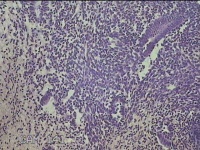

宫腔内容物

性别

女

年龄

45岁

临床诊断

子宫内膜息肉

一般病史

月经量增多10年,B超检查发现宫腔异常回声半月余。

标本名称

大体所见

灰白暗红色不规则碎组织1.5x1.3x0.7cm一堆。